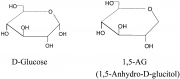

| 18:30, 12 באוקטובר 2017 | GlycoMark3.jpg (קובץ) |  |

17 קילו־בייטים | Motyk | 1 | |

| 18:28, 12 באוקטובר 2017 | GlycoMark2.png (קובץ) |  |

31 קילו־בייטים | Motyk | 1 | |

| 18:27, 12 באוקטובר 2017 | GlycoMark1.png (קובץ) |  |

29 קילו־בייטים | Motyk | 1 | |

| 18:25, 12 באוקטובר 2017 | GlycoMark.png (קובץ) |  |

12 קילו־בייטים | Motyk | 1 | |